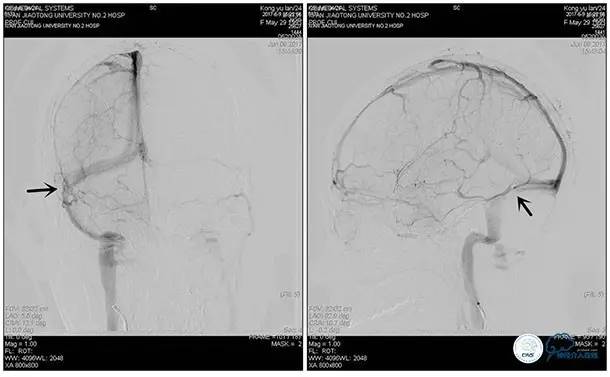

术中造影

5ml/s,总量8ml,压力100~150

术后造影

术毕远近端压力差为:0

术中测压

远端压力:530mmH2O

近端压力:120mmH2O

狭窄较前有改善

术中测压:

远端:520mmH2O,

近端:190mmH2O。

术后远、近端压力差为:0